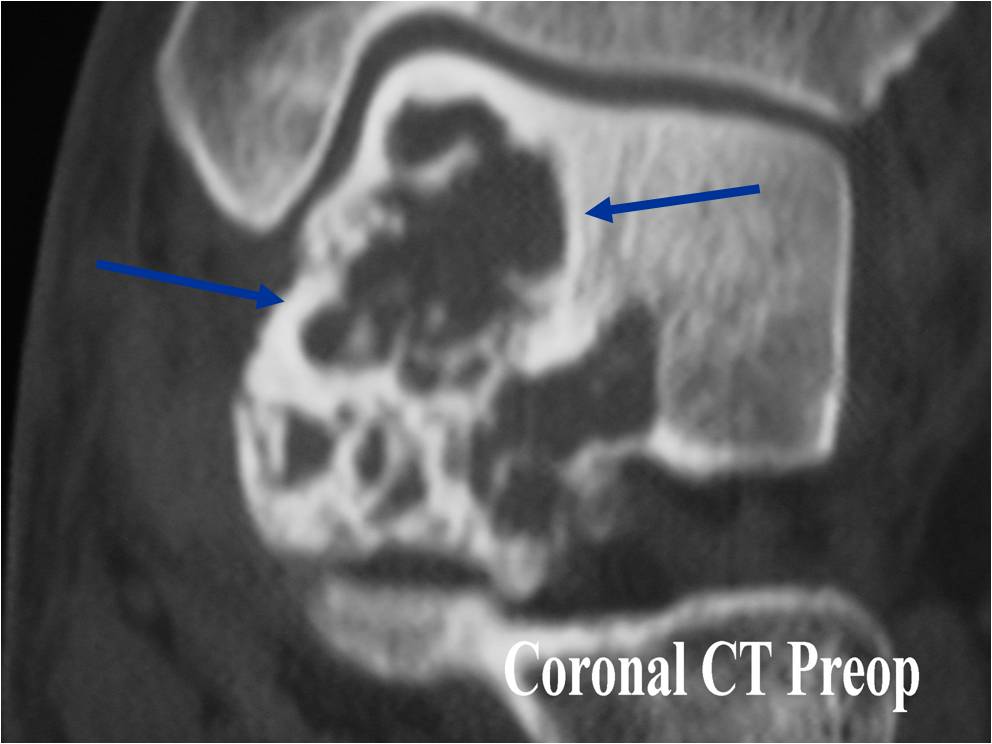

- (CT appearance)

- Most useful for detecting subtle mineralization not apparent on X-rays

- Useful for identifying intact periosteum around any expansile soft tissue component

- surrounding thin reactive shell of bone/mineralization (Egg Shell Rim of Calcification)

- helps place the tumor in a benign category

- helps evaluate:

- bony quality

- extent of bone and cortical destruction

- whether the subchondral plate of bone adjacent to the articular cartilage has been destroyed or is intact